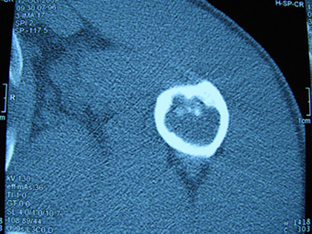

标题: X6404B:肱骨骨质破坏(CT片) [打印本页]

标题: X6404B:肱骨骨质破坏(CT片)

男,50岁,左肩部轻微疼痛,活动不便5个月就诊,近十天加重,无红肿热,间断理疗治疗无好转,既往5个月前左肩轻微拉伤史

骨巨?动脉瘤样骨囊肿?

内生软骨瘤。

内生软骨瘤。

内生软骨瘤?-----------

年纪大了,先要排除转移瘤。

髓腔内软组织肿块并斑片状钙化,考虑高分化软骨肉瘤可能性大。

考虑骨巨或动脉瘤样骨囊肿。

内生软骨瘤可能性大,期待结果。

孤立性骨囊肿。

内生软骨瘤可能性大

其内可见钙化,考虑软骨源性肿瘤,内生软骨瘤可能

但由于年龄较大,恶性软骨肉瘤待排

肱骨头内巨大软组织肿块并斑片状钙化,内生软骨瘤?骨巨细胞瘤?软骨粘液样纤维瘤?期待结果!

髓腔内软组织肿块并斑片状钙化,考虑高分化软骨肉瘤可能性大。

内生软骨瘤可能性大

肱骨头内巨大软组织肿块并斑片状钙化,内生软骨瘤?骨巨细胞瘤?软骨粘液样纤维瘤?期待结果

考虑内生软骨瘤?骨巨细胞瘤?

内生软骨瘤?骨巨细胞瘤?

先要排除转移瘤。